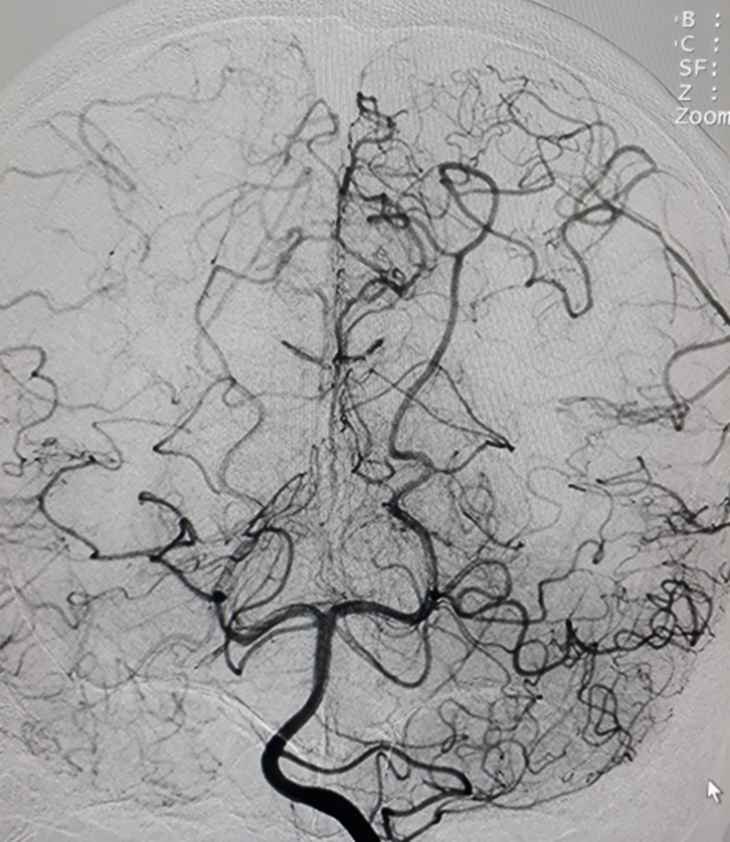

Một bệnh nhân trẻ tuổi, CLVT mạch máu não nghĩ nhiều đến hình ảnh của bệnh Moya Moya, vì vậy bệnh nhân được chỉ định chụp DSA mạch não để khẳng định chẩn đoán đồng thời tiên lượng khả năng điều trị bệnh.

Hình chụp DSA động mạch cảnh trong phải và trái: hẹp khít động mạch não giữa hai bên đoạn M1.

Hình chụp DSA động mạch cảnh trong trái: hẹp khít động mạch cảnh trong trái đoạn mấu giường.

Hình chụp DSA động mạch đốt sống: bàng hệ cho hệ tuần hoàn trước từ hệ thống tuần hoàn sau

Bệnh Moya Moya là bệnh lý mạch máu hẹp tại gốc một số động mạch lớn trong sọ thuộc tuần hoàn trước (thuộc động mạch cảnh trong). Quá trình hẹp dần dần nên cơ thể thích nghi bằng các tuần hoàn bàng hệ bù cho vùng thiếu hụt tuần hoàn. Tuần hoàn bàng hệ phát triển tại chỗ hẹp bằng rất nhiều mạch máu nhỏ và yếu, dễ hình thành các phình mạch nhỏ và vỡ gây chảy máu não. Nếu tuần hoàn bàng hệ một lúc nào đó không đủ cấp máu cho não sẽ gây nên nhồi máu não tái đi tái lại. Trên chụp mạch, các mạch nhỏ tại chỗ hẹp tạo nên hình “những làn khói tỏa” (puff of smoke). Bệnh lấy tên một bác sĩ người Nhật là người đầu tiên mô tả về bệnh này trong y văn.